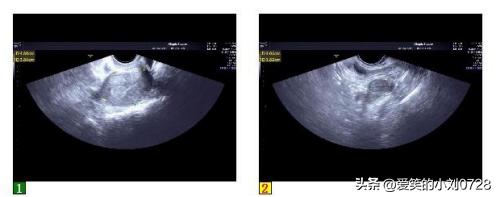

患者按照医嘱积极配合,能够按时到医院进行复查,复查白细胞计数(图2),检查结果显示指标已下降并恢复到基本正常范围,复查超声(图3)提示:盆腔肿物消失。患者下腹疼痛消失,体征正常,阴道分泌物正常,无异味,患者对治疗效果表示非常满意。

超声提示:盆腔肿物消失